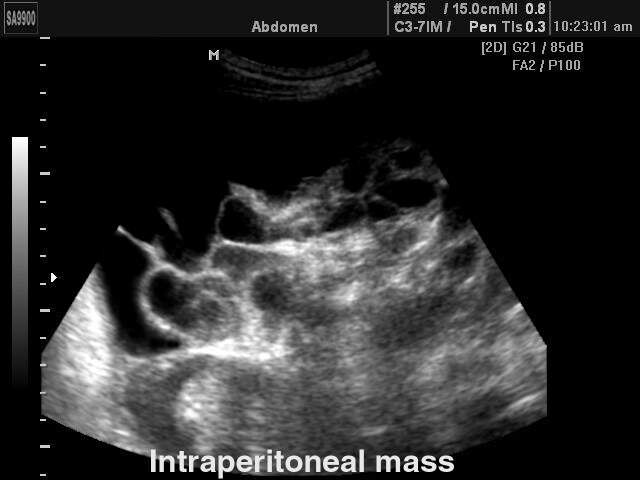

• Пациенты с подозрением на опухоли: УЗИ может быть использовано для оценки наличия опухолей или других образований в кишечнике.

• Оценить состояние органов: Метод помогает визуализировать стенки кишечника, выявлять воспалительные процессы, опухоли и другие аномалии.